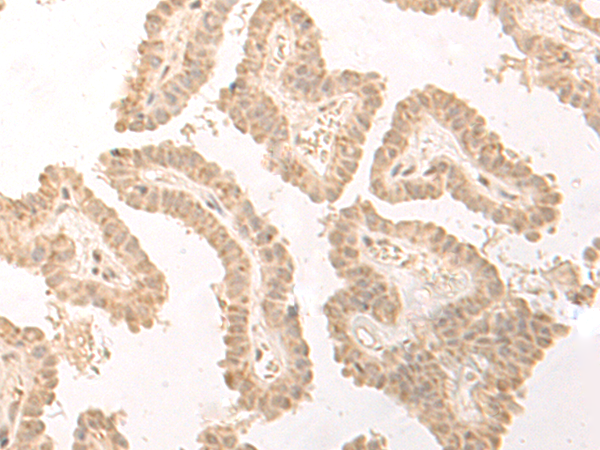

分类: 科研抗体货号: P09798别名: ESG; ESG1; GRG1应用: WB,IHC反应种属: Human, Mouse